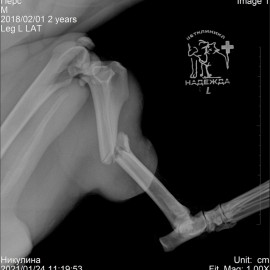

Наш пациент после автотравмы. Был проведен остеосинтез левой голени, в ходе которого была установлена динамическая титановая пластина с винтами. Так же были наложены серкляжные швы из титановой проволоки. Состояние пациента хорошее. Лапой пользуется активно.

Снимок 1-2 до операции.